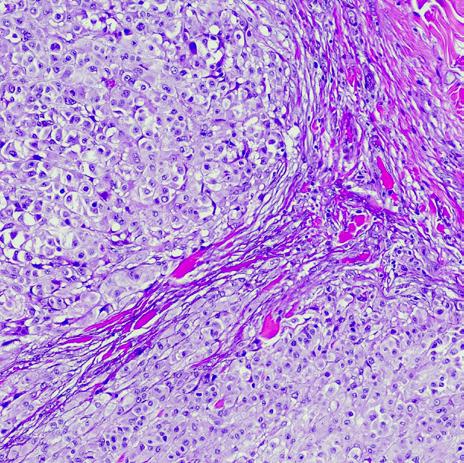

Advancements in Immunotherapy and Targeted Therapy in Gastrointestinal Cancers

reatment of gastrointestinal (GI) cancers has evolved in the last two decades, which has contributed to significant improvements in the outcomes of many GI cancers. Immunotherapy and targeted therapy have revolutionized the treatment of patients with GI cancers in recent years. Not only have those treatments provided patients with better clinical outcomes but also have resulted, in many situations, in reduced treatment-related toxicity. As a result of developments in immunotherapy and targeted therapy, oncologists can provide patients, in many cases, with additional options beyond standard cytotoxic chemotherapy.

Immunotherapy is a novel treatment that allows the immune system to better recognize and fight cancer cells. Immunotherapy is currently being used in many stages of the treatment of GI cancers. In this section, we will summarize the advances in immunotherapy and describe its role in various phases of the treatment of GI cancers.

In this review, we will describe the recent advancements in immunotherapy and targeted therapy with a special focus on gastrointestinal cancer.

Targeted Therapy

Targeted therapy is a novel treatment that has improved outcomes of many cancers including gastrointestinal cancers. Targeted therapy is a highly sophisticated treatment that recognizes certain genetic changes that lead to the growth and spread of cancer cells. Once the targeted therapy attaches to its target genetic alteration, it helps control the growth and spread of cancer cells. Targeted therapy options are being explored in various GI cancers. Some remain investigational while others have been adequately researched and are now approved by the FDA for routine use in patients with GI cancers that harbor special genetic changes.

Targeted therapy options continue to increase and have resulted in significant improvement in patient outcomes. Genetic mutations are typically tested using genetic next-generation sequencing (NGS), which has advanced significantly in the last few decades. NGS tests can test tumor biopsy or blood samples for genetic changes that can act as targets for targeted therapy. In the next section, we will summarize genetic changes related to various GI cancers and discuss potential targeted therapy treatments that have shown promising activity against those genetic changes.